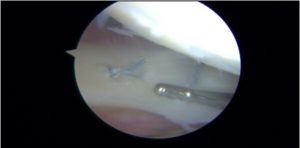

All inside meniscal fixation using mainly two FasT-Fix® devices (Smith and Nephew)